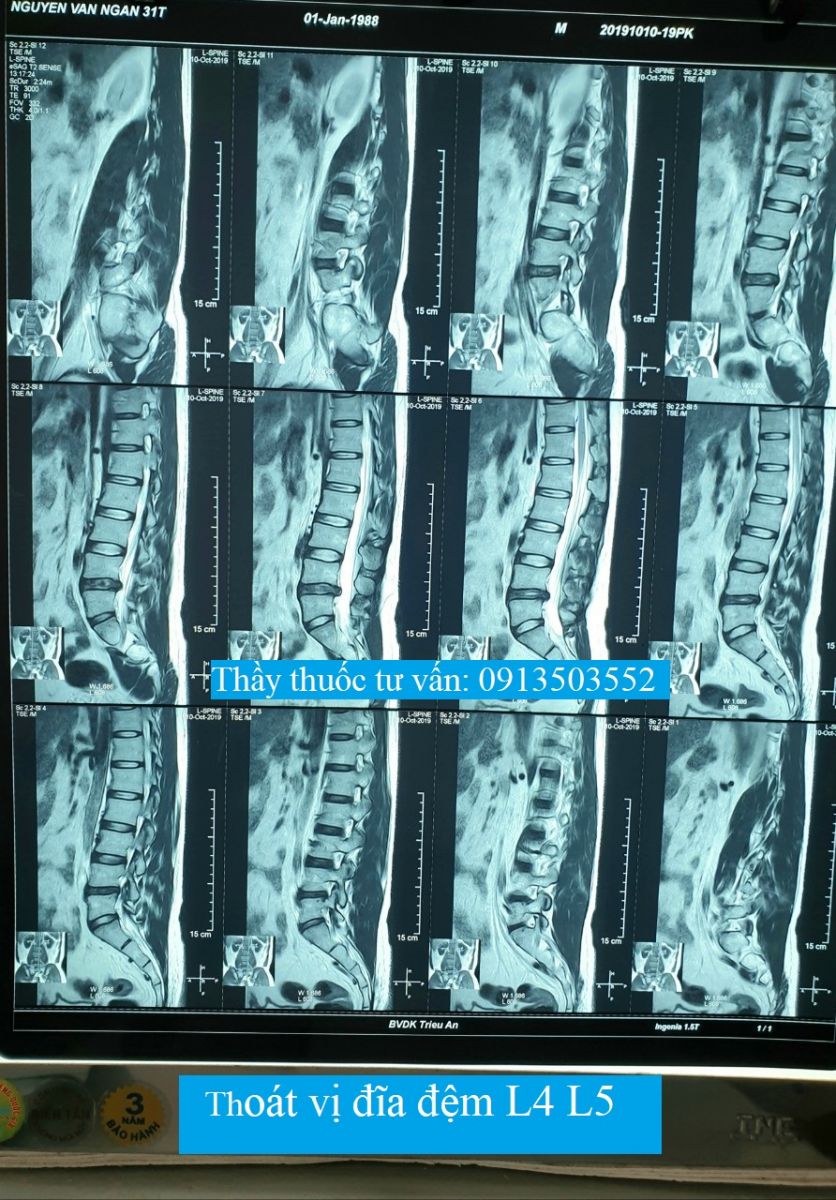

Thoát vị đĩa đệm L4 L5Thoát vị đĩa đệm L4 L5, kích thước 6mm, chèn ép vào rễ thần kinh L5 hai bên và gây hẹp ống sống (đường kính trước - sau #6mm)❮ đọc tiếp ❯